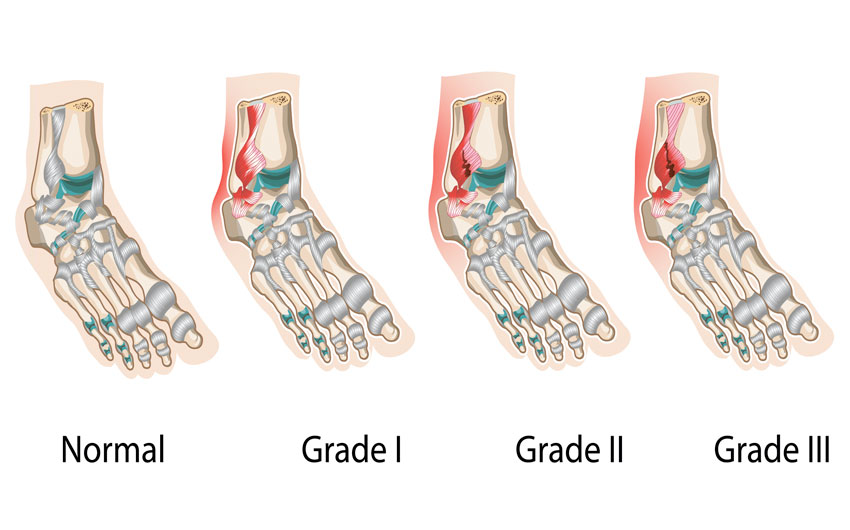

Анатомические фото голеностопного сустава и его суставных поверхностей